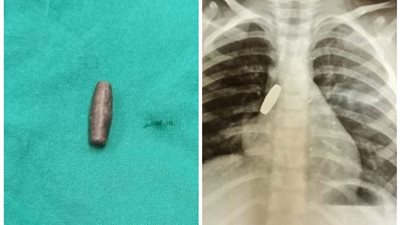

إنقاذ طفلة ابتلعت طلقة خرطوش في المنيا (صورة)